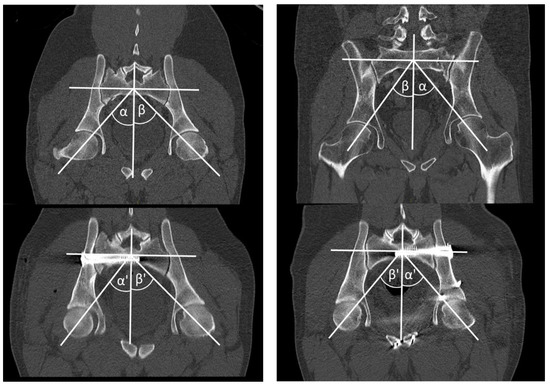

Figure 3 illustrates the measurement of the mechanical load-bearing axis in MPR 2. MPR 2 is a reconstruction through the center of the first sacral body and through both centers of the femoral head. This reflects the biomechanical axis of the lower extremity.

Figure 3.

Measurement of the mechanical load-bearing axis in MPR 2. ILBA (α) and CLBA (β) in preoperative CT scan and ILBA (α’) and CLBA (β’) in postoperative CT scan.

- -

- Ipsi-lateral load-bearing angle (ILBA): We measured the angle between the orthogonal to the sacral axis diameter at the center of the body S1 and the line through the center of the femoral head of the affected side.

- Contra-lateral load-bearing angle (CLBA): We measured the angle between the orthogonal to the sacral axis diameter at the center of the body S1 and the line through the center of the femoral head of the contra-lateral side.